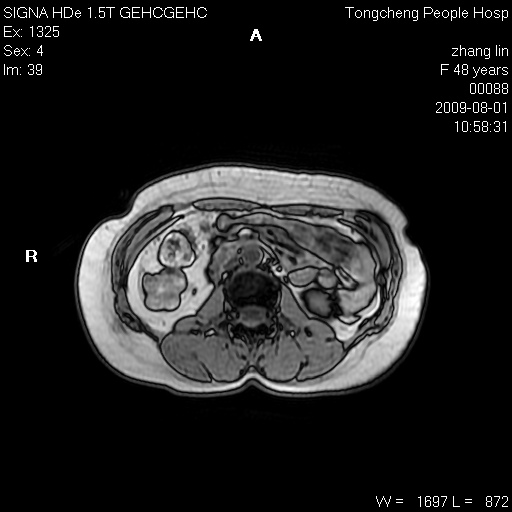

女,48岁。健康体检,彩超发现右肾占位性病变。平素健康。

临床诊断:右肾占位性病变,性质待定(囊肿?肿瘤?)。

上中腹部mr平扫+增强扫描,图像如下:

右肾上极见一类圆形病灶,t1wi呈等信号t2wi呈等高混杂信号,三期增强无强化,边界清---考虑囊肿出血。

同反相位均表现为等信号,病变无强化,考虑含蛋白的囊肿可能,弥散加权相或许有些帮助,

肝囊肿

慢性胆囊炎